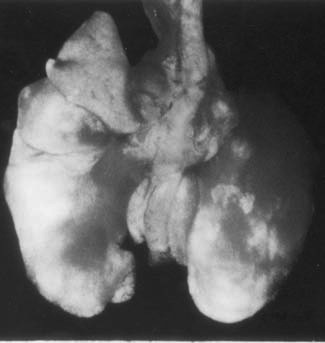

Lungs from an immunocompetent mouse that exhibited generalized signs of illness in addition to chattering. What is the most likely etiology and mouse strain?

Sendai virus

DBA/2 are highly susceptible to lethal infection.

P&B, p 37